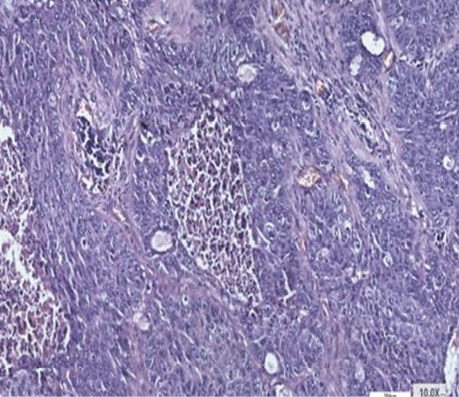

На основі вищезгаданих фундаментальних досліджень при вивченні серійних зрізів операційного матеріалу хворих на РЛ особливу увагу ми звернули на наявність ділянок, характерних для БАРЛ за усіма клітинними ознаками і характером росту. Нами виявлено в кожному препараті переважно плоскоклітинного і переважно залозистого РЛ ділянки БАРЛ. У гістологічних препаратах залозистого РЛ такі структури траплялися часто, іноді займали великі площі з усіма характерними ознаками росту цього типу новоутворення. У гістологічних препаратах усіх хворих на переважно плоскоклітинний рак теж відмічалися ділянки БАРЛ різного розміру. Крім того, нами виявлені, не описані в медичній літературі, цікаві показові структури, коли РЛ росте в альвеолі, переповнює її, проростає базальну мембрану і солідним пластом росте в міжальвеолярному просторі (див. рис. 6). Подібне розростання пухлини може бути причиною наявності різних строкатих ділянок, що може ускладнювати визначення гістологічного типу РЛ. Патологоанатоми в процесі гістологічної діагностики РЛ не фіксують наявність ділянок БАРЛ у зв’язку з тим, що в новій Міжнародній гістологічній класифікації пухлин легень ВООЗ цей тип раку належить до підтипу залозистого РЛ, і тільки окремо виділяється вистілковий його варіант (lipidic).

Рис. 6. Плоскоклітинний рак. Проростання раковими клітинами мембрани альвеоли і подальший солідний ріст. Howell, Black. Збільшення ×600